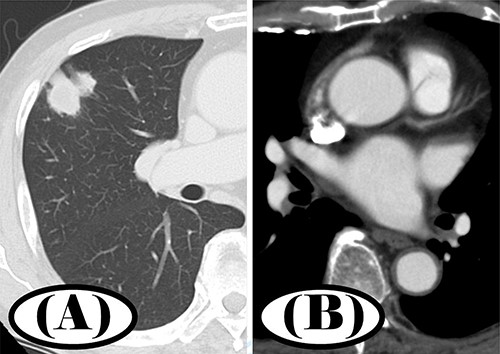

On post-operative day 7, the patient developed right lower extremity coldness as well as pain. Contrast-enhanced CT showed a thrombus in the right superior PVS (Fig. 2B). No vessels were depicted peripherally from the right popliteal artery (Fig. 2A). We diagnosed the patient with acute arterial occlusion of the right lower extremity. Emergency thrombectomy was performed and the patient’s symptoms quickly improved.

Contrast-enhanced CT before and after thrombectomy; (A) no peripheral vessels were depicted beyond the right popliteal artery before thrombectomy; (B) thrombus was seen in the right superior PVS before thrombectomy; (C) thrombus disappeared in the right superior PVS after thrombectomy.

After the thrombus was removed, the patient was started on oral clopidogrel (75 mg/day) and edoxaban (30 mg/day). One week later, a chest CT scan showed resolution of the thrombosis in the right superior pulmonary vein (Fig. 2C). He was discharged from the hospital 3 weeks after the surgery. Five years post-operatively, the patient has shown no signs of recurrence.